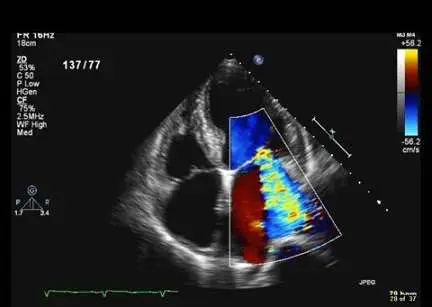

如圖所示, 依此心臟超音波可以得到的資訊,下列何者錯誤?

針對apical four-chamber心臟超音波(echo)彩色多普勒影像解讀,重點在於辨識心房大小、二尖瓣逆流、心包積水,以及適當判斷瓣膜狹窄與否。

- 切面:典型apical four-chamber(A4C)view,探頭置於心尖向上,顯示左、右心房與左、右心室四腔結構。

- 二尖瓣區彩色多普勒:見到一大束血流在Systole期間穿過二尖瓣向左心房噴射,彩色信號以紅(向探頭流動)為主,並有藍色混雜,符合中度至重度mitral regurgitation(MR)之典型表徵。

- 左心房:相較右心房與心室,左心房顯著擴大,房壁圓弧更為突出,提示慢性容量負荷下之房室擴張。

- 心包腔:環繞心臟外緣未見無回聲流體帶,排除心包積水。

- 主動脈瓣:此A4C view並非評估aortic valve狹窄之適當切面,畫面也未見高流速jet或CW Doppler量測,無法支持存在AS。